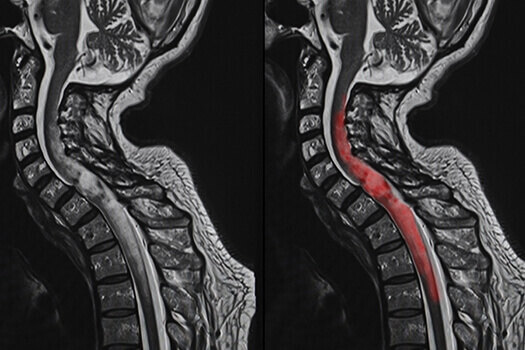

决定脊髓肿瘤手术恢复时间的一个重要因素是肿瘤的不同解剖位置。脊髓瘤种通常根据它们与脊髓和硬脑膜的解剖关系来分类,硬脑膜是一种包含脊髓、脊髓神经和脊髓液的薄膜。硬脑膜外的肿瘤称为硬膜外肿瘤,而硬脑膜内的肿瘤称为硬膜内肿瘤。硬膜内肿瘤被进一步定义为是否存在于脊髓内或脊髓外。脊髓内的肿瘤称为硬膜内髓内肿瘤;脊髓外的肿瘤称为髓外硬膜内肿瘤。

另一方面,硬膜内肿瘤存在于硬脑膜内,很少见。这些肿瘤通常是原发性的,这意味着它们起源于硬脑膜或其周围,而不是转移的结果。它们通常不影响脊柱的稳定性,并且这些肿瘤的手术通常不需要金属植入物的稳定。因此,这些手术通常都不是大手术。对于这些肿瘤,手术和恢复受患者术前神经状态的影响更大。如果病人在手术前有严重的神经问题,这将影响恢复的时间,即使手术本身是一个小问题。另一个因素是肿瘤是否在髓内(存在于脊髓内)。如果肿瘤是髓内的,手术需要打开脊髓来切除肿瘤。这通常会影响腿部的感觉,需要程度的术后康复和恢复,这是接受过髓外肿瘤手术的患者可以避免的。